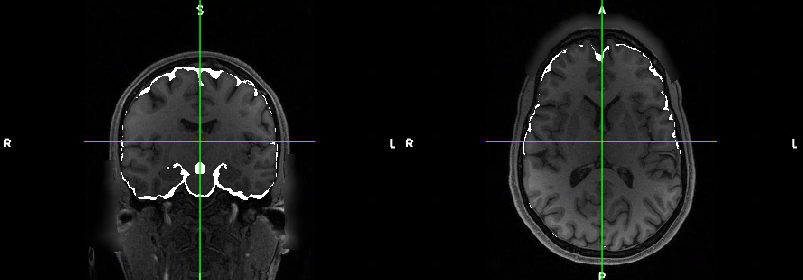

As we have been reviewing our Auto_EACSF output, we have noticed that the output for T1w input is missing significant chunks of CSF in comparison with the output for T1w and T2w input (especially in the posterior regions). This can be seen in the attached png file.